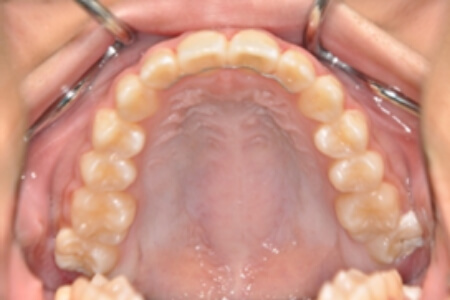

| 治療内容の詳細 | 初診時10歳の女性で、全体的ながたつきを主訴として来院されました。 検査の結果、交叉咬合を伴う、アングルⅠ級不正咬合と診断しました。 治療としては、反対咬合を改善するための装置で上顎前歯部を前方にだすと同時に上あごを広げ、セルフライゲーションブラケット装置(デーモンシステム)で歯の配列を行いました。 治療期間は2年11か月でした。 |